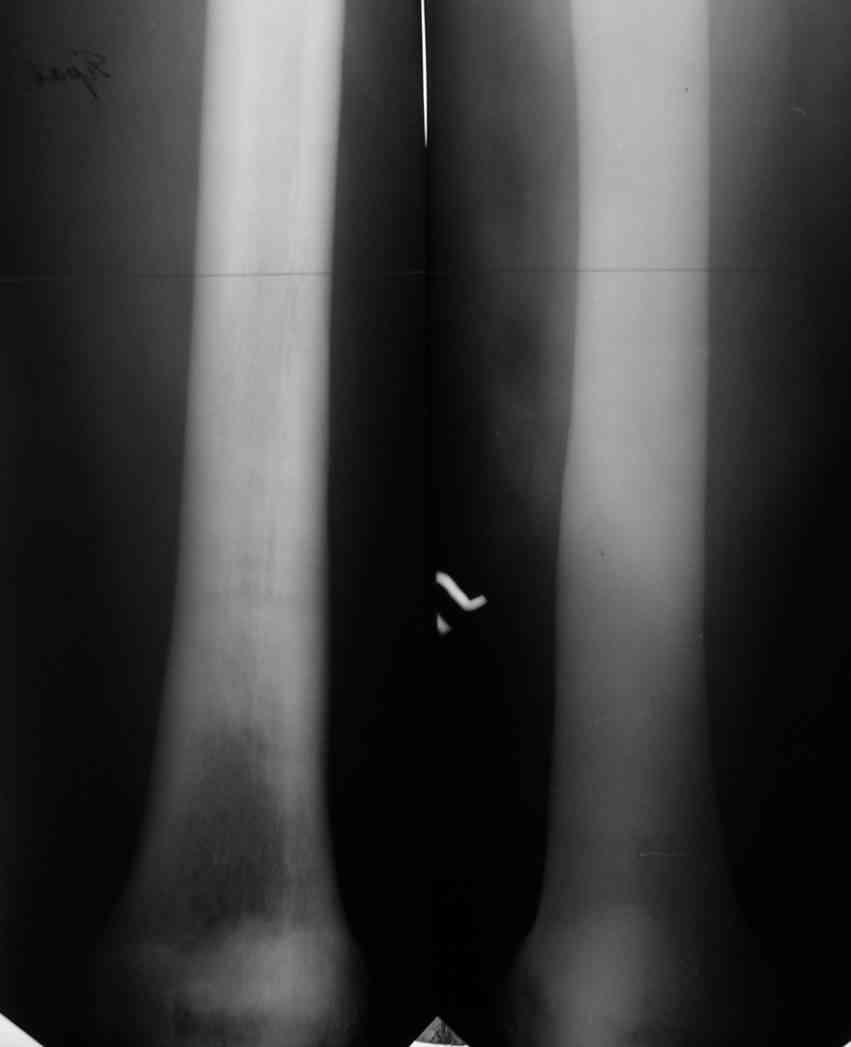

Уважаемый Константин Иванович! Полностью согласен с проф. Михайловым, данный случай не похож на мраморную болезнь, при которой имеется резкое, строго симметричное и генерализованное уплотнение костной ткани (остеопетроз), и кость оказывается построенной преимущественно из гомогенного компактного костного вещества. Для примера привожу случай из архива нашего института (бедренные, плечевые кости и таз, рис 1,2,3)

Изменения структуры костей у Вашего пациента больше похожи на полиоссальную форму фиброзной дисплазии или болезнь Педжета, возможены также инфаркты костного мозга б.берцовых костей. К сожалению, качество снимка не очень хорошее, непонятно, сохранен ли кортикальный слой б.берцовых костей по передней поверхности.

Для примера привожу случай из архива американской ассоциации рентгенологов (ACR) - развитие злокачественной фиброзной гистиоцитомы на левой б.берцовой кости у пациента с множественными инфарктами костного мозга (рис 4,5 - левая, рис 6 - правая)